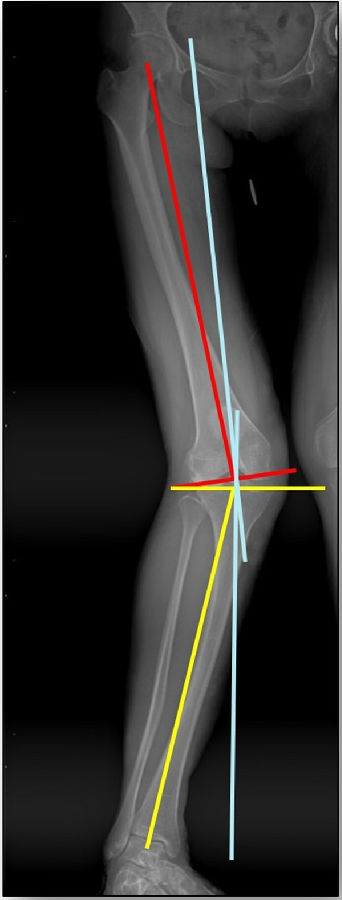

患者二,女性,膝外翻,膝外侧疼痛。通过做畸形分析后发现,该患者同时存在股骨侧畸形、胫骨侧畸形和关节内畸形(LDFA=82°,MPTA=104°,JLCA=6°)。

对于这类病人如何进行术前设计的关键点就在于目标力线应如何设计。要在骨性截骨的时候纠正骨性畸形,关节内畸形要通过关节内的方法解决。因为JLCA不平行,所以要同时画股骨侧关节线和胫骨侧关节线,并垂直于股骨侧关节线做出股骨侧目标力线,垂直于胫骨侧关节线做出胫骨侧目标力线。

根据各自目标力线,分别计算股骨内侧闭合和胫骨内侧闭合角度。

此患者股骨内侧闭合6°,经股内侧闭合13°。

术后影像